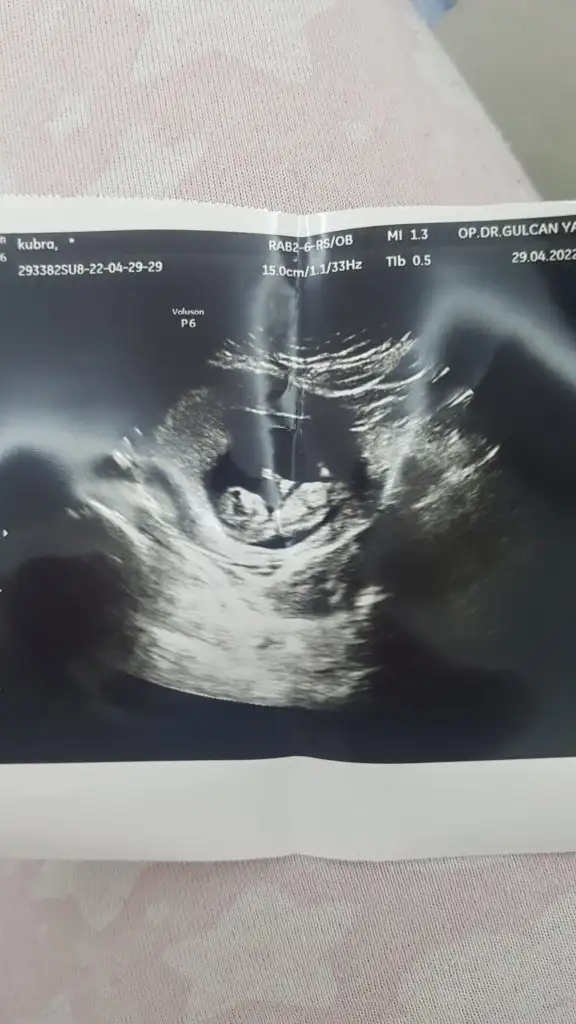

karından ultrasonmerhaba ben bi tahmin alayım bu görüntüler 6 haftalık iken

paşa gıbı canımMerhaba 6 haftalık vajinal ultrason tahminde bulunurmusunuz